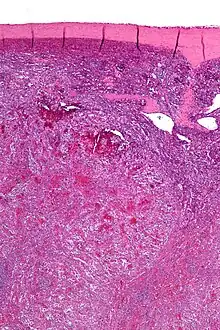

| Low magnification micrograph of a littoral cell angioma. H&E stain. | |

Littoral cell angioma, abbreviated LCA, and formally known as littoral cell angioma of the spleen, is a benign tumour of the spleen that arises from the cells that line the red pulp.[1]

Littoral cell angiomas show in CT scans. They are diagnosed by pathologists by taking a sample of the tumour via Fine Needle Aspiration or Core Needle Aspiration or from a splenectomy. Histologically, they have anastoming small vascular channels and cystic spaces with papillary projections.[2]